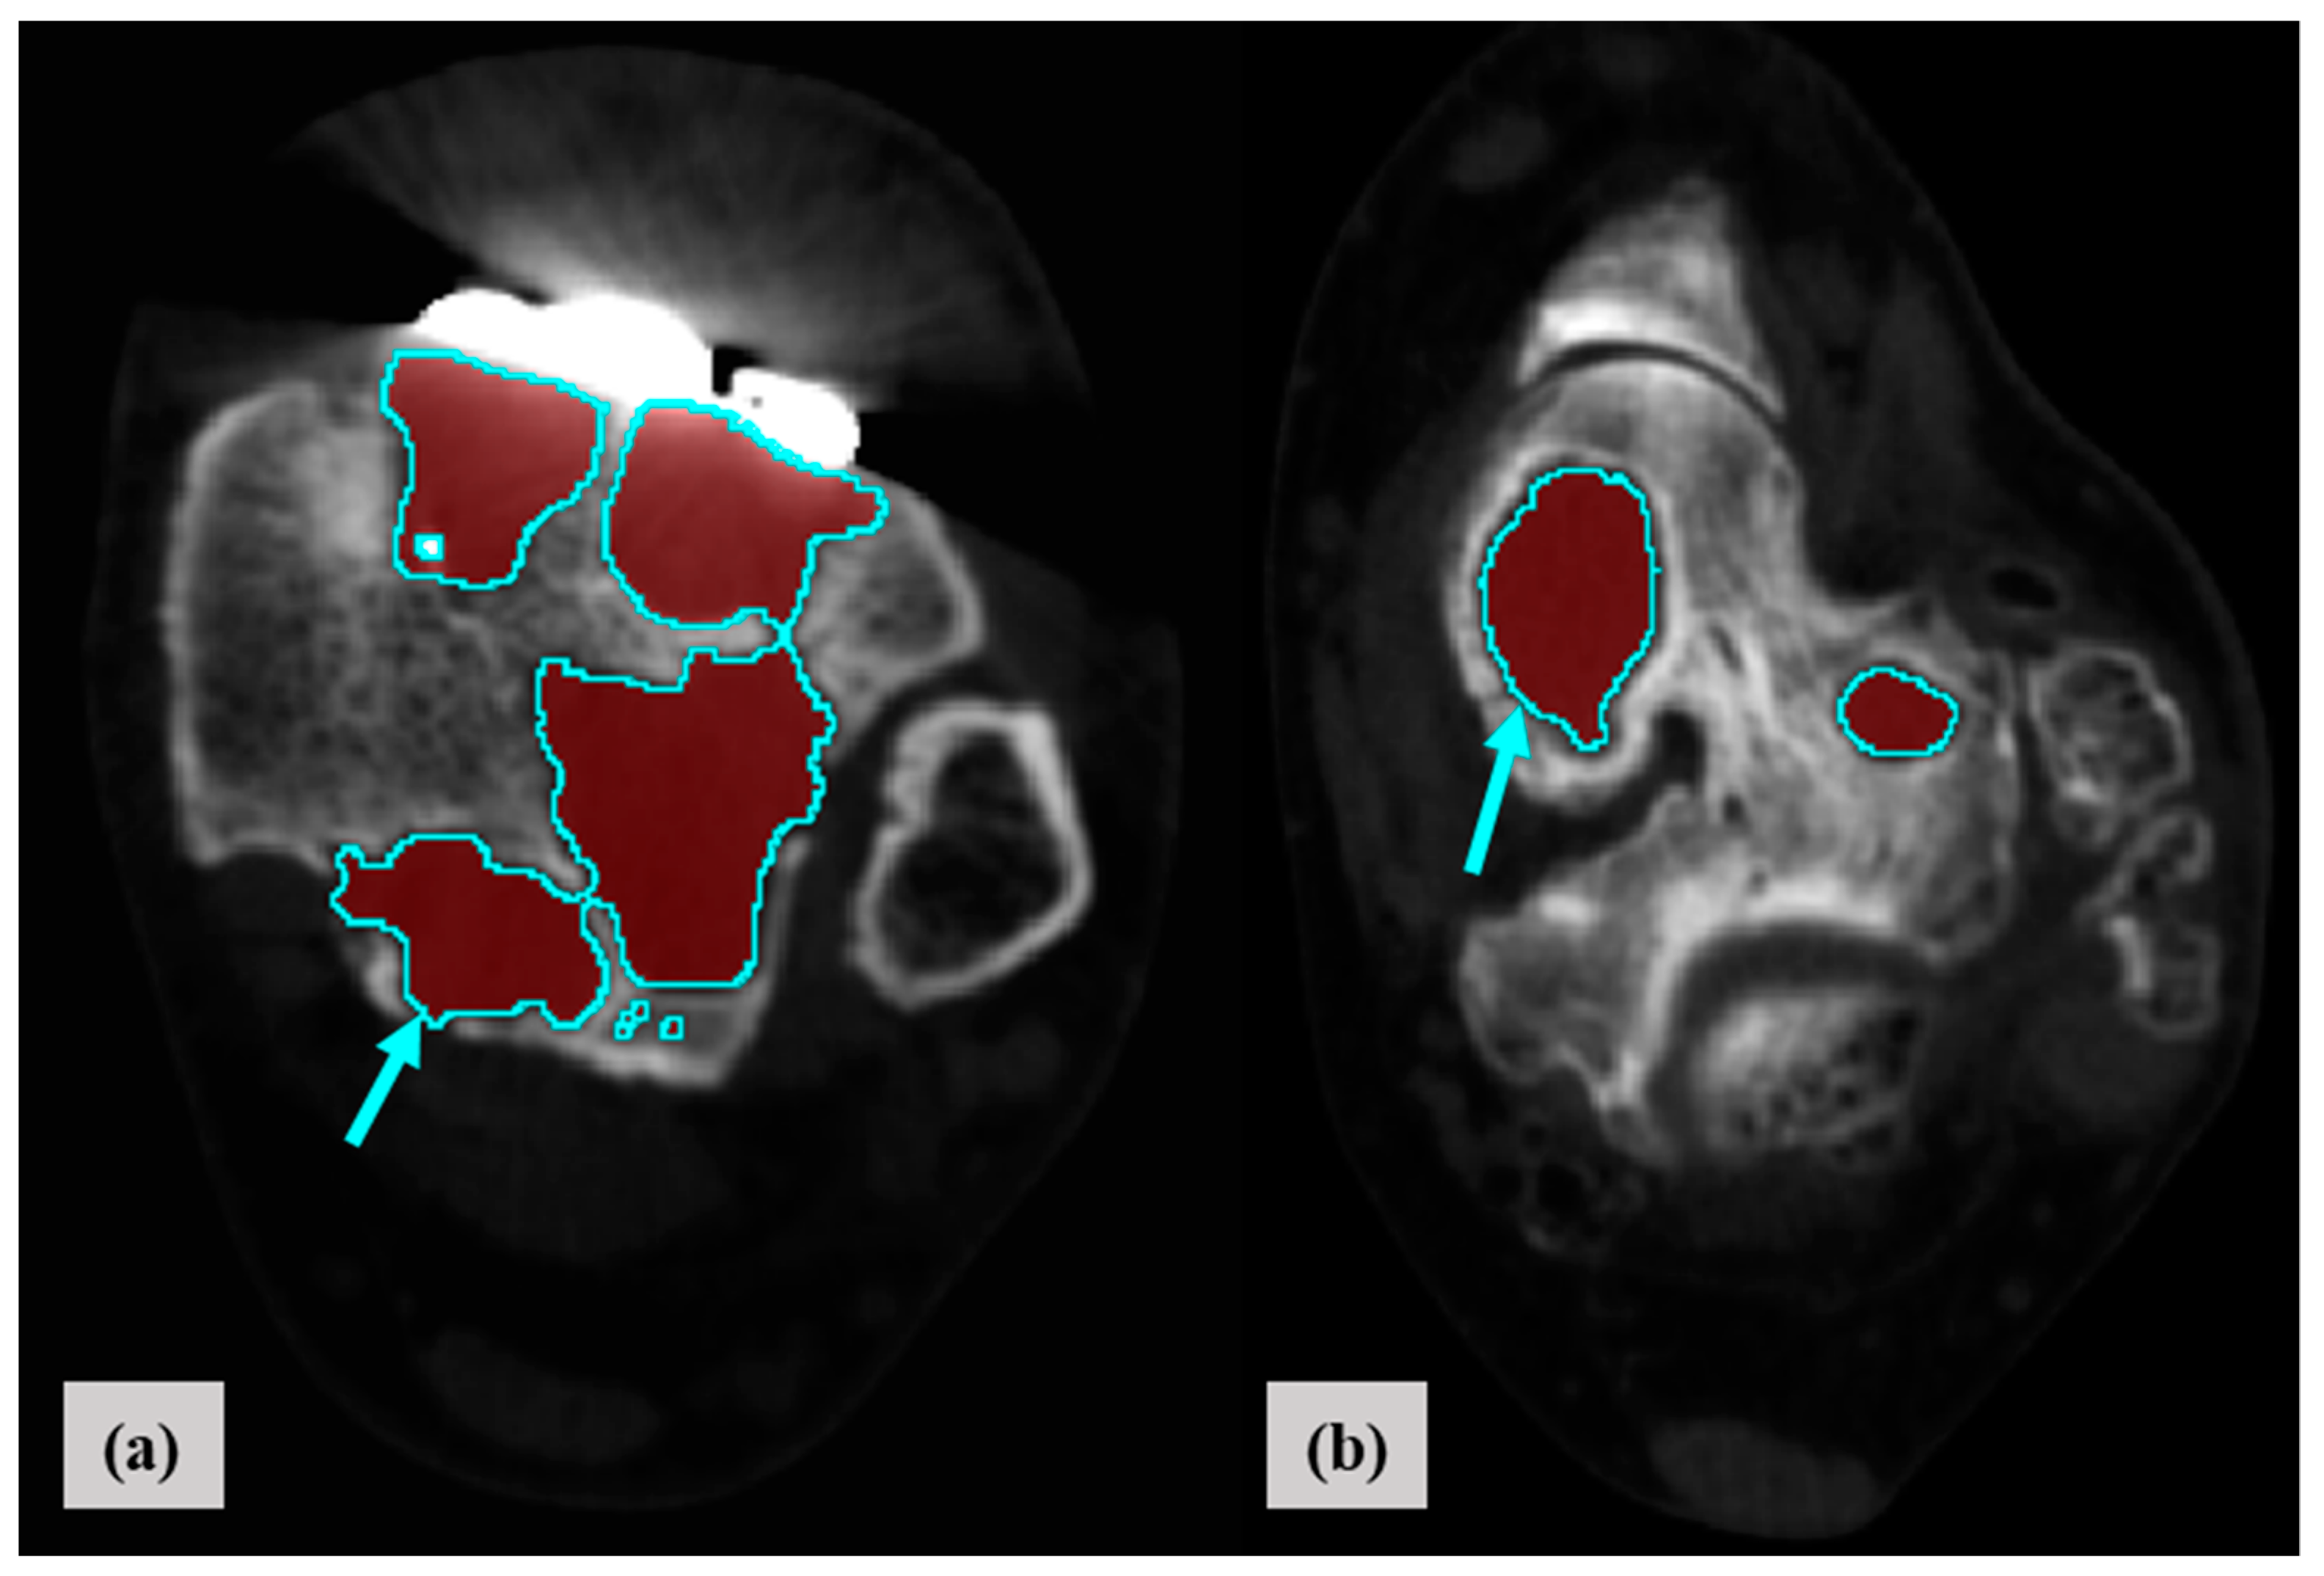

2.3. Measure of Location, Distribution, and Normalized Volume of Osteolysis